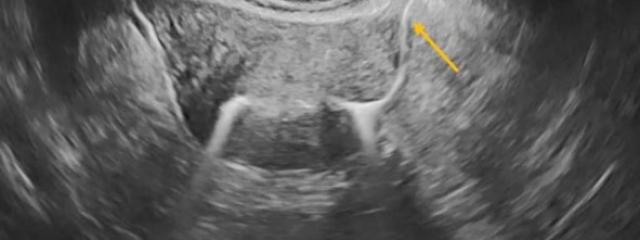

Ψάχνετε ολοκληρωμένη και εξατομικευμένη διερεύνηση υπογονιμότητας; Στο ιατρείο μας παρέχουμε πλήρη διάγνωση και προτάσεις θεραπείας, σε ένα μόνο ραντεβού.